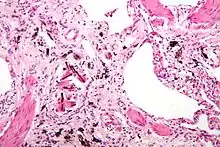

Micrograph of asbestosis (with ferruginous bodies), a type of pneumoconiosis. H&E stain. | |